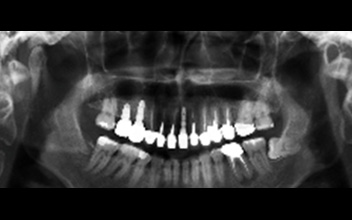

左側正中門牙缺牙,缺牙處植入人工牙根。